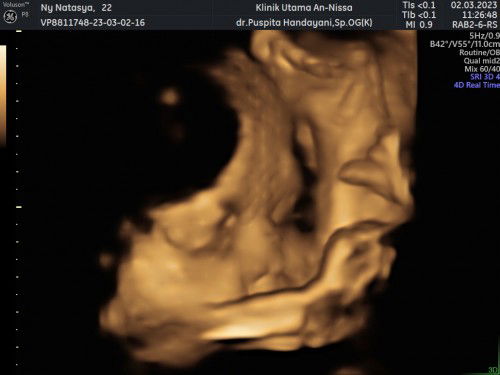

Posisi janin

Udah 35 minggu tapi janin masih sungsang nih bun solusinya gimana ya?😭